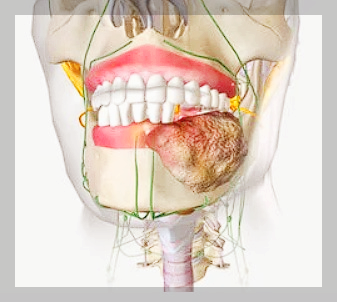

구강암이란 입안이나 입술에 나타날 수 있는 암을 총칭하여 부르는 것입니다. 입 안에 생기는 위치에 따라 치주암, 설암, 구강저암 등으로 나뉘게 되는데요. 보통은 혀, 잇몸, 혀 밑바닥, 볼 점막 순으로 암이 많이 발생합니다.

특히 초기 증상 중에서 구내염과 치주병, 치은염 등과 증상이 비슷하여 간과하기 쉬운 증상인데요. 상처를 입은 기억이 없는데 입 주변 2주 이상 지속되는 통증이 있거나, 입/목 주변이 붓거나 혹이 생겼을 때, 입 안쪽 또는 입술에 붉거나 흰 반점이 생길 수 있습니다.

잇몸에서 반복적으로 출혈이 있거나, 이가 갑자기 흔들리거나 이를 뽑고은 후 상처가 아물지 않을 때에는 구강암을 의심할 수 있습니다. 구강암은 전체 암의 5~6%를 차지하며 점차 발병률이 증가하고 있는 추세입니다.